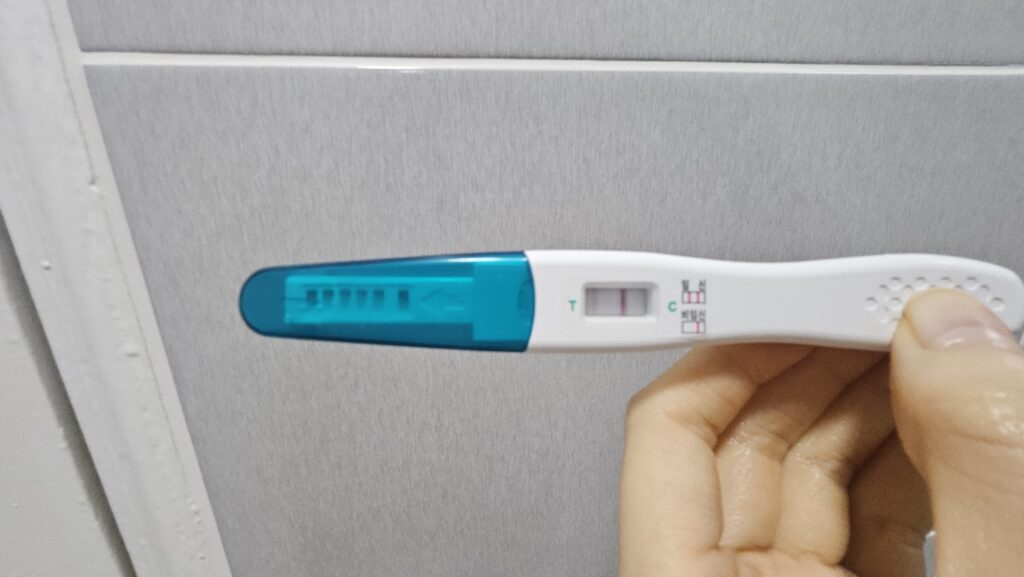

푸켓 갔다 와서 처음 얼리 임테기를 해 봤는데, 한 줄이 떴었고 첫 임신 시도라서 당연한 귀결이라고 생각했다. 이후 샤워하고 할 거 하고 있다가 1시간 정도 지난 이후에 잠깐 다시 테스트기를 보니 희미한 두 줄..;;

15분이 지난 테스트기는 신뢰도가 떨어진다는 얘기를 들어서 아닐 거라고 생각했는데, 임신한 친구에게 보여주니 빼박 임신이란다.

이후 다시 테스트기를 해봤고, 확실하게 두 줄을 확인했다..!